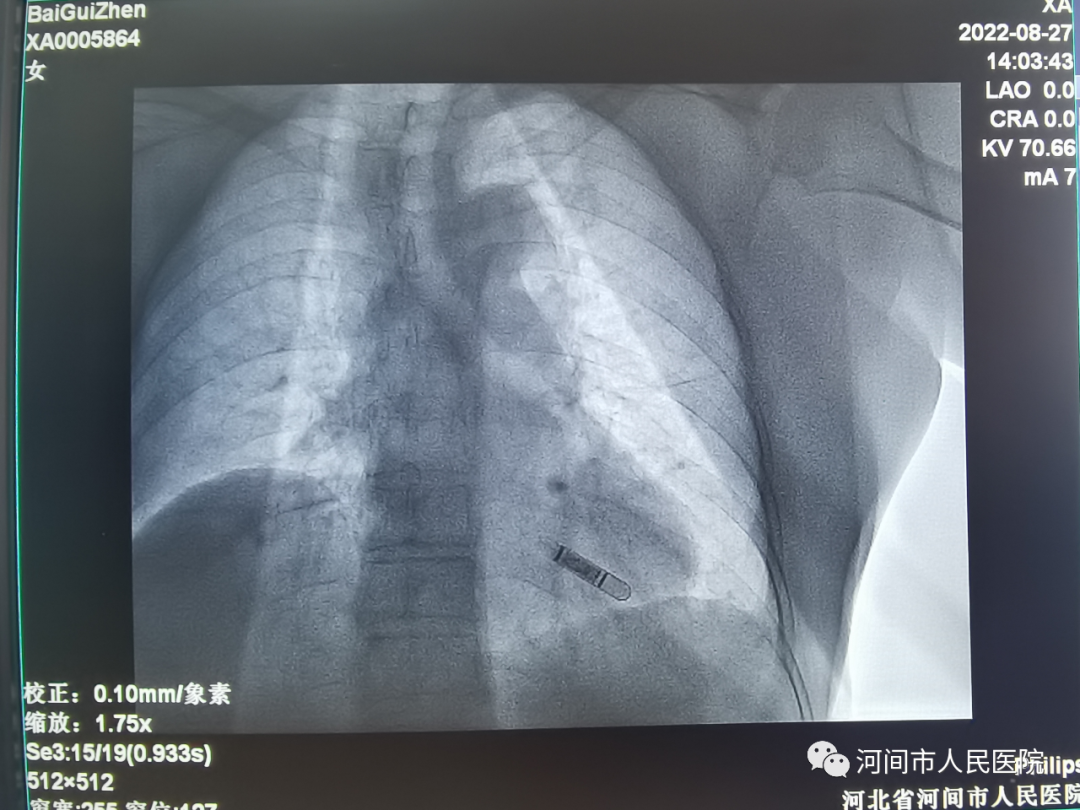

2022年8月27日,我院心內(nei) 二科副主任醫師李彥起、彭娜,為(wei) 一名暈厥患者成功安裝植入式心電事件監測器(又稱植入式Holter),為(wei) 滄州區域內(nei) 醫院首例植入患者。

植入式Holter如曲別針大小

完善相關(guan) 檢查並排除手術禁忌後,在局麻下,於(yu) 患者左胸切開約1厘米的切口,做好相應囊袋將心電記錄器置入皮下後縫合,手術時間約15分鍾。手術操作簡單、創傷(shang) 小,患者幾乎感覺不到痛苦。